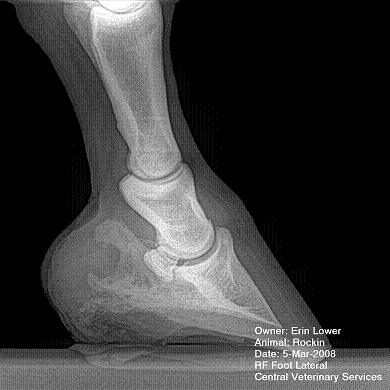

So, Rockin's x-rays were sent to a radiologist and he confirmed "normal" changes in the navicular bones for a horse her age, but slightly more significant ones in the right (sore) foot.

She also has sidebone in both fronts, but apparently that isn't causing any discomfort.

Finally, she has a "small chronic exostosis on the lateral aspect of the proximal phalanx" which, according to the radiologist, shouldn't be causing discomfort but I have read that these can be mild-to-moderately painful... I wouldn't mind another opinion on that.

I will attach as many images as possible from her x-rays (there are many different views). I don't have any pics of the feet as someone deleted them from my camera before I could download them. I'll try to take pics next time she is trimmed. Please, anyone with knowledge of hooves, give any opinions that you might have (especially Dr. O!)

Hello Erin and welcome back,

I cannot rule out lesions based on these images but I will take your radiologist's word that he does not see significant lesions. The exostosis on the RF would be above the level of a well conducted PDN which I believed blocked the lameness before?

Could you tell me why the need for a wedge pad?